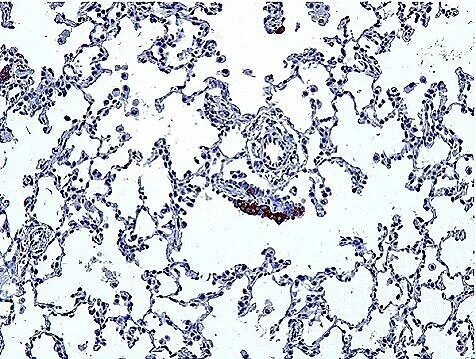

NEHI_Patient.png

Abnormal PNECs in a NEHI patient